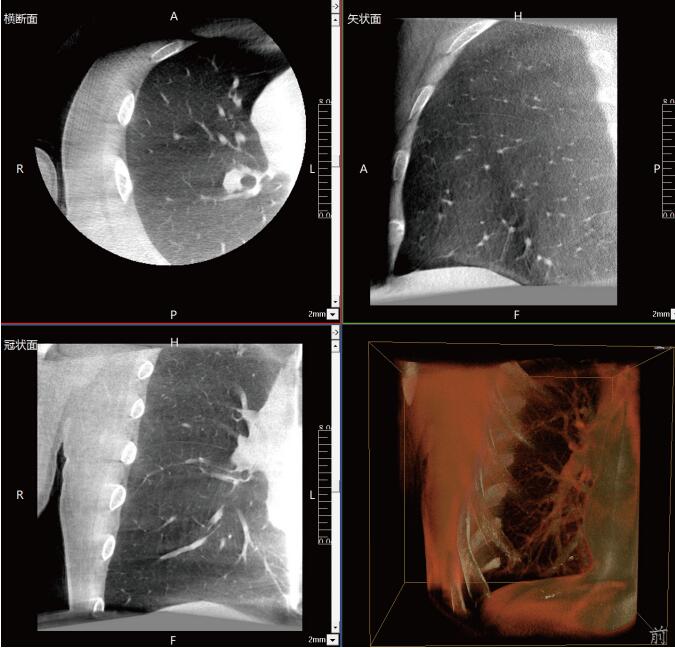

滿足肺結(jié)節(jié)活檢、肺結(jié)節(jié)切除、肺結(jié)節(jié)消融治療等各類術(shù)式的術(shù)中影像要求:

常規(guī)流程下需要術(shù)前CT室內(nèi)的引導(dǎo)定位,再轉(zhuǎn)入手術(shù)室進(jìn)行胸腔鏡手術(shù),在轉(zhuǎn)運過程中有氣胸、肺出血和導(dǎo)針脫落的風(fēng)險。使用大功率平板三維C形臂PLX C7600,可在手術(shù)室內(nèi)一站式完成肺部三維影像重建,在穩(wěn)定呼吸的條件下,亞亳米級定位肺結(jié)節(jié)位置,有效規(guī)避穿刺路徑附近的血管、氣管等重要解剖結(jié)構(gòu),術(shù)中確保穿刺安全有效。同時可大幅降低輻射劑量,減少射線對醫(yī)患的傷害。